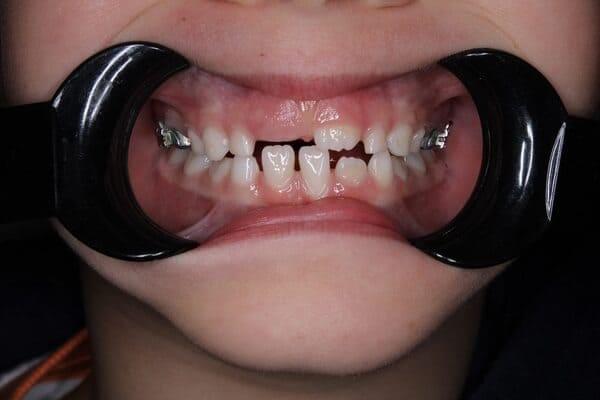

Дівчинка 2 років, але зуби вже мають глибокі ураження із залученням у запальний процес пульпи (“нерва”) зуба. На жаль, так трапляється і зволікати в такому випадку не можна. Було проведено лікування в умовах анестезіологічного забезпечення під контролем досвідченої анестезіологічної команди. Передні зубчики відновлено естетичними коронками, на жувальних зубчиках проведена герметизація фісур, а один вже має глибоке ураження карієсом, тому теж покритий коронкою. Одразу після лікування ясна можуть виглядати дещо травмованими, але за кілька днів вони повністю відновляться.